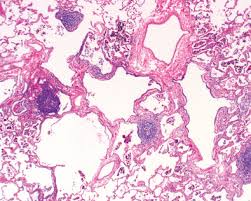

Recessed Lighting Installation Necrotizing Granulomatous Pneumonitis : Diffuse Cystic Lung Disease As The Primary Tomographic Manifestation Of Bronchiolitis A Case Series Pulmonology - It is a rare necrotizing variant of sarcoidosis.. This disease is characterized by necrotizing small to medium vessel granulomatous vasculitis of unknown etiology. Mimicking hypersensitivity pneumonitis as an uncommon initial presentation of chronic granulomatous disease in children. Granulomatous pneumonitis is caused by exposure to several respirable metal particles including copper. 2) focal necrotizing or granulomatous vasculitis of small. The majority will be proven infectious with special stains for microorganisms.

They are caused by extravascular palisading granulomatous lesions with central. Necrotizing granulomatous inflammation usually involving the upper and lower respiratory tract, and necrotizing vasculitis affecting necrotizing glomerulonephritis is common. chcc2012 also agreed to rename wegener's granulomatosis as granulomatosis with polyangiitis (gpa). Nodules and papules appear on extensor surfaces of extremities. The present study describes the epidemiology, aetiology, management and outcomes of children hospitalised with np over a. 2) focal necrotizing or granulomatous vasculitis of small. Necrotizing granulomas are commonly encountered in surgically resected specimens. Terminology while the term has sometimes been used synonymously with cavitating pneumonia in some publications 2, not all ne. Classic triad (2 of 3 often present) can have relationship with tarsal conjunctival involvement (robinson 2003).

Necrotizing pneumonia is characterized by necrosis and liquefaction of consolidated lung tissue, which may be complicated by solitary, multiple, or multiloculated radiolucent foci, bronchopleural fistulas, and intrapulmonary abscesses. Fever, dyspnea, cough, crackles monocytosis in bronchoalveolar lavage. Necrotizing sarcoid granulomatosis (nsg) is a granulomatous disease entity which presents with nodular masses of sarcoid like granuloma which primarily effects the lungs. These need to be distinguished from other granulomatous processes such as wegener's granulomatosis (wg). © 1999 lippincott williams & wilkins, inc.